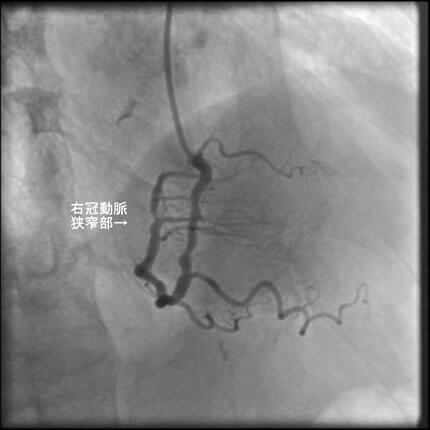

1番目の患者さんは80歳の男性です。この方の危険因子は高血圧、高脂血症、喫煙です。この方の冠動脈造影と腹部CT画像を示します。図1-1から1-8の画像は全て全てこの患者さんの画像です。

図1-1 右冠動脈造影

よく解らないと思いますが、冠動脈に多数の狭窄があることと冠動脈が「こぶ状変化(医学用語で瘤状変化)」を生じているのが解ると思います。